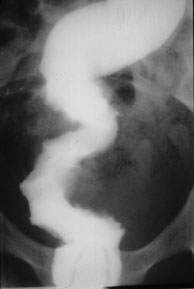

GASTRIC SARCOID COLONIC SARCOID

The granulomatous process involves the gastric antrum leading to irregular nonspecific narrowing.

Irregular narrowing of the rectosigmoid due to sarcoidosis has the appearance of inflammatory disease or malignancy .